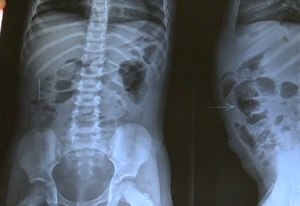

Uma menina de apenas três anos tem ao menos três agulhas de costura pelo corpo e quatro já foram removidas. A tia da criança denunciou à polícia que o padrasto é suspeito da agressão.

A garota vivia com a mãe na cidade de Atalaia, mas mudou-se para a casa de uma tia em Jacaré dos Homens, cidade do interior de Alagoas. A menina se queixou de dor e, após exames, descobriram as agulhas.

A mãe da vítima também foi ouvida pela polícia e disse já ter retirado quatro agulhas do corpo da filha e não soube dizer quem as teria colocado. A polícia informou que segue investigando o caso.